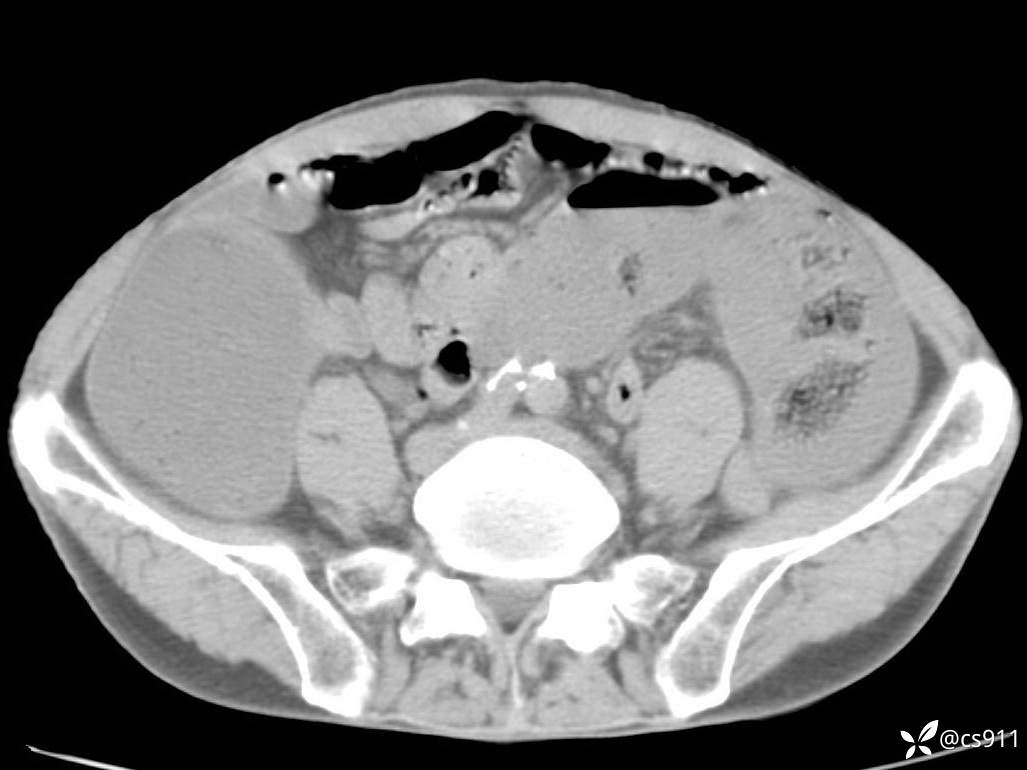

急腹症之急诊CT,原因?答案公布

男,77岁,腹痛、腹胀伴恶心呕吐1天。呕吐胃内容物,非喷射性呕吐,有咖啡色样胃内容物,诉有胃穿孔病史。查体:全腹平,下腹部压痛,全腹无反跳痛,叩诊呈浊音,移动性浊音阴性,肠鸣音减弱,1-2次/分。肛检:直肠未扪及明显肿物,可触及大量粪块。

血淀粉酶(AMY) HH 1859 U/L 35-135